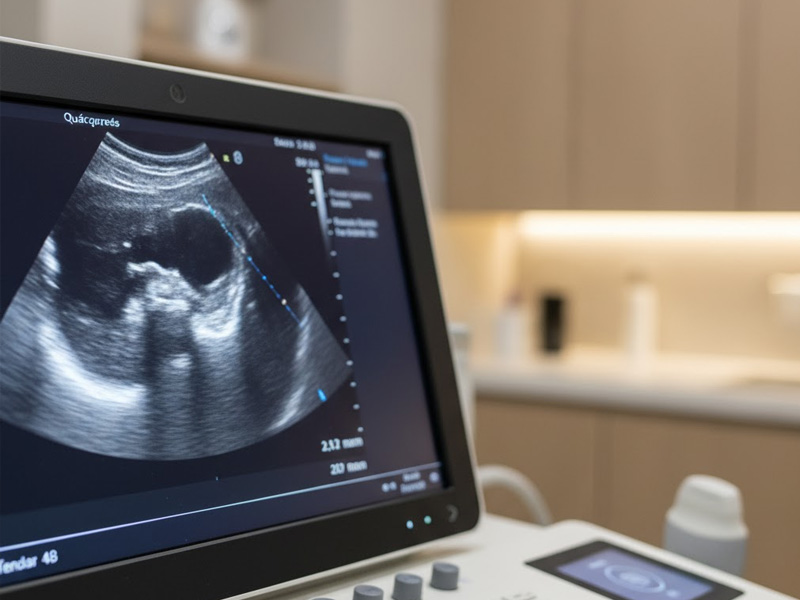

Esta herramienta nos permite observar en tiempo real músculos, tendones, ligamentos y nervios, ofreciendo una visión detallada del estado de los tejidos y ayudando a planificar tratamientos más efectivos y seguros.

La ecografía musculoesquelética es una técnica de diagnóstico por imagen que utiliza ultrasonidos para visualizar estructuras del sistema locomotor.

- La sonda del ecógrafo emite ondas de ultrasonido que rebotan en los tejidos.

- El equipo transforma esas ondas en imágenes que el fisioterapeuta interpreta en tiempo real.

Este procedimiento permite una exploración inmediata y dinámica, ideal para detectar lesiones y valorar su evolución sin necesidad de radiación.

La ecografía se combina con el razonamiento clínico del fisioterapeuta. Gracias a ella, podemos identificar con mayor exactitud el tipo de lesión, su extensión y características.

Además, el paciente puede ver en pantalla su lesión, entendiendo mejor su situación y aumentando su implicación en el tratamiento.